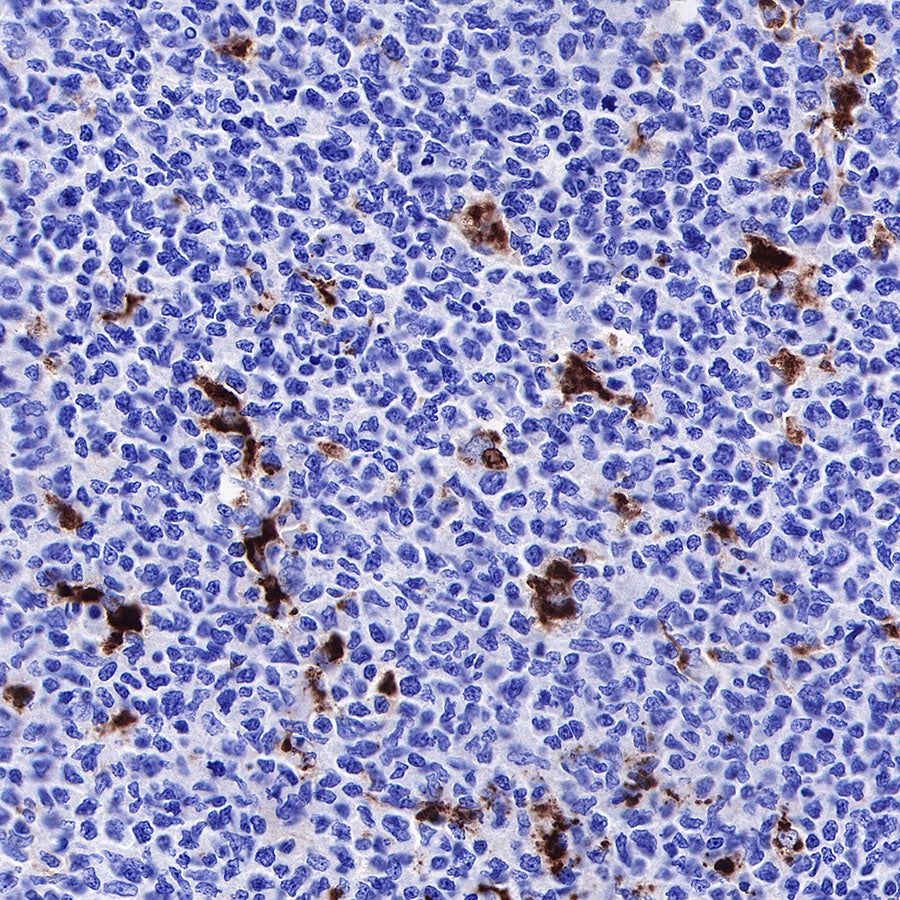

IHC shows positive staining in paraffin-embedded human diffuse large B-cell lymphoma. Anti-CD68 antibody was used at 1/1000 dilution, followed by a HRP Polymer for Mouse & Rabbit IgG (ready to use). Counterstained with hematoxylin. Heat mediated antigen retrieval with Tris/EDTA buffer pH9.0 was performed before commencing with IHC staining protocol.